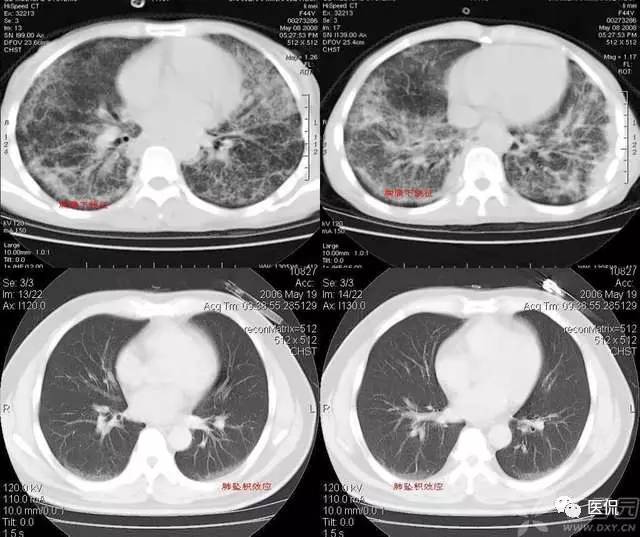

树芽征

是指病变累及细支气管时,由于炎性渗出物或分泌物堵塞细支气管,CT表现为小叶中心分枝状线影和与其相连的细支气管横断面结节影,状如春天里挂满枝芽的“树”,即“树芽征”。是细支气管扩张、阻塞的特征影像之一。肺小叶是构成肺的最小结构单位,直径约10 25mm,小叶之间为结缔策划间隔,每个肺小叶都有一支小叶支气管(直径≤lmm)和小叶肺动脉进入,二者皆位于小叶的中心。CT不能显示直径小于2mm支气管,故正常小叶支气管CI’扫描时不显示,但当小叶支气管发生病变时,CT就可以显示出来。

树芽征的小叶中心结节影和分枝状线影是同一病理结果的不同影像表现,二者的病理基础都是细支气管的扩张与阻塞,CT横断面像呈平行走向的细支气管表现为分枝状线影,呈垂直或斜向走行者表现为结节影。原发或继发于细支气管的病变(如炎症)可导致细支气管壁增厚、细支气管扩张,当同时伴有分泌物潴留时,支气管“树”状如春天里一棵挂满枝芽的“树”。随着气道的继续扩张和肺实质病变的出现,支气管“树”会进一步扩展。当大气道扩张伴有周围小气道气体潴留时,就类似于支气管疾病时大气道堵塞所形成的“指套征”。

树芽征的相关疾病有:肺支气管的感染性病变,免疫性疾病如变应性支气管肺型曲霉菌病,先天性疾病如囊性肺纤维化及纤毛运动异常综合征(Dyskinetic’s综合征),肿瘤性疾病如少年型喉气管支气管乳头状瘤病,吸人刺激性物质,弥漫性全支气管炎及阻塞性细支气管炎,血管性疾病等等。